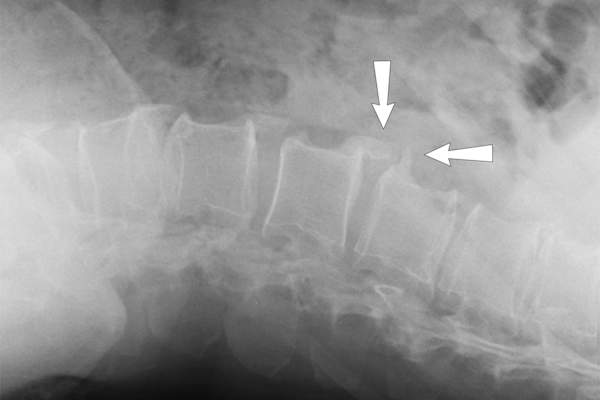

骨性关节炎是由x光诊断的

OA和RA都要求你提供病史并进行临床诊断。但阿什尼博士说,对于诊断OA, x光也很重要。x光图像可以显示骨头之间的空间是否变得更窄,这是软骨丢失的迹象。它们可以揭示骨赘的存在。阿斯卡里博士说,磁共振成像(MRI)也可以用来检测软骨和周围组织的更详细的变化。